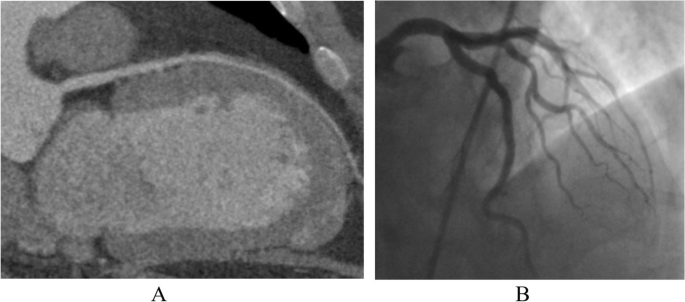

This study is a prespecified secondary analysis of the CAD-Man trial and is included in the published study protocol [8]. To be eligible for the study and randomization to coronary CT or ICA, patients needed to have suspected CAD and a clinical indication for ICA. In addition, patients had to have a maximum of two of the three criteria for typical angina pectoris (retrosternal chest discomfort, precipitation by exertion, and prompt relief within 30 s to 10 min by rest or nitroglycerine) [8]. The following exclusion criteria were used for the trial: two or more positive tests indicating ischemia, no sinus rhythm, signs of myocardial infarction (persistent ST segment elevation, creatine phosphokinase-MB > 24 U/L, or pulmonary edema due to ischemia), refusal or were incapability of providing informed consent, inability to hold the breath for 5 s, younger than 30 years, or history of or receiving dialysis [8]. The coronary CT procedure included both a non-contrast coronary artery calcium acquisition and a post-contrast CT angiography. No patients had prior coronary CT or ICA. After study enrollment and provision of informed consent, patients were randomly assigned to initial evaluation with either CT or ICA as previously described [8]. If CT was positive for CAD on non-invasive angiographic assessment, patients were then recommended to undergo ICA to confirm the diagnosis before initiation of treatment. Explanations about the imaging tests to the patients prior to their performance were provided by clinical staff. Images were shown during the ICA using on-site monitors by the interventional cardiologists in charge and after the CT procedure using workstations by the radiologists in charge using curved multiplanar reformations and three-dimensional renderings (Fig. 1).

Patient imaging examples. Example of negative coronary CT (A) and negative ICA (B). A Multiplanar reconstruction of the left main and left anterior descending of a patient randomized to coronary CT angiography without pathological findings, CAD was excluded. B Patient example of normal invasive coronary angiography showing strong vessels of the left coronary artery and its branches of the left anterior descending and left circumflex artery, CAD was excluded